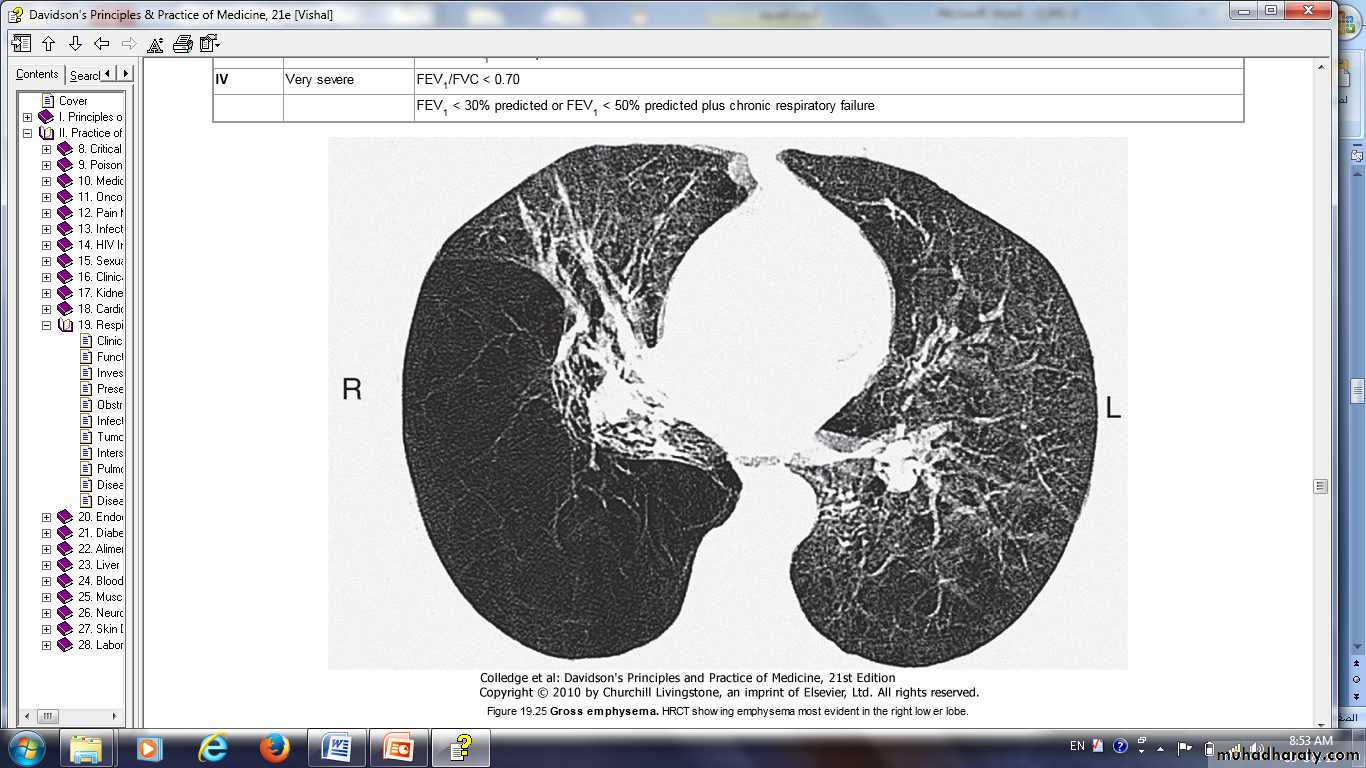

Gross emphysema. HRCT showing emphysema most evident in the right lower lobe.

This 42-year-old man had smoked 20 cigarettes a day since the age of 14. He presented with a 5-year history of progressive breathlessness and could walk only 100 m. He had severe airway

obstruction, with an FEV1 of 0.5 l and a transfer factor for carbon monoxide and transfer coefficient reduced to 30% of predicted values. High-resolution CT shows extensive emphysematous bullae with dilated distal airspaces, cysts and destruction of alveolar

architecture. Levels of ????1-antitrypsin were unrecordable.